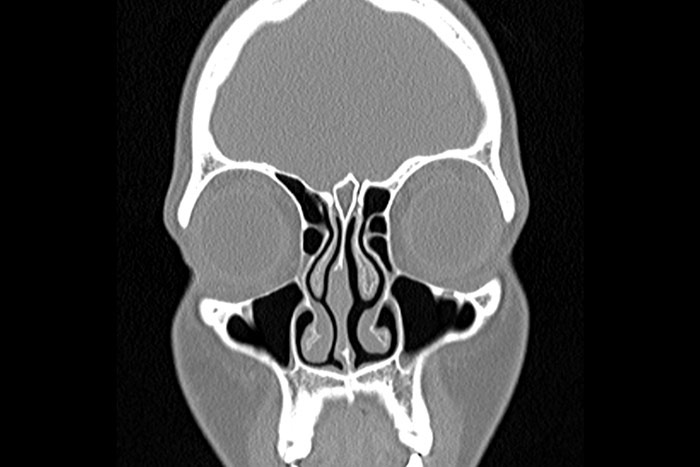

سی تی اسکن بینی چیست؟

سی تی اسکن بینی یکی از آزمایشات لازم قبل از جراحی بینی می باشد که در آن با کمک اشعه ایکس عکس های لازم از ساختمان بینی گرفته و در اختیار جراح بینی قرار داده می شود تا در اتاق عمل از آن ها استفاده کند. البته این نکته را در نظر داشته باشید که معمولا عکسبرداری از بینی برای آن دسته از افرادی که می خواهند عمل زیبایی انجام دهند ضرورتی ندارد اما اگر جراحی زیبایی همزمان با مشکلات بینی مانند پولیپ بینی انجام شود حتما به سی اسکن نیاز پیدا خواهید کرد.

در این روش فرد باید رو به شکم دراز بکشید تا امواج اشعه ایکس بتوانند با کنار زدن بافت های مزاحم به داخل ساختمان بینی نفوذ کرده و عکس های لازم را تهیه کنند. این عکس ها به جراح در تشخیص ضایعات بینی و محل قرارگیری آن ها کمک می کند، این مشکلات عبارت اند از :

تعداد پولیپ های بینی و محل قرارگیری آن ها در ساختمان بینی

تشخیص میزان عفونت در سینوس ها

تشخیص انحراف بینی

سی تی اسکن صورت تصاویری تولید می ‌کند که حفره های سینوس پارانازال بیمار را نشان می دهد. سینوس های پارانازال فضای توخالی و پر از هوا هستند که در اطراف حفره بینی قرار دارند و با تهیه این تصاویر می توان سینوس ها و مشکلات و یا گرفتگی های آن را بررسی کرد.